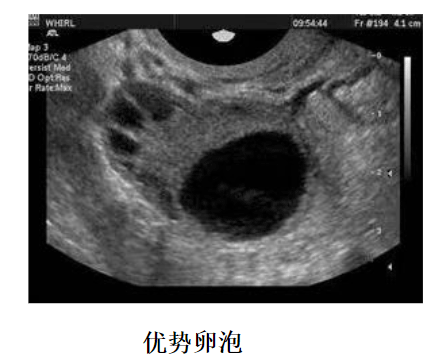

卵泡监测方法就是阴道B超检测,如果想要更加准确的判断卵泡发育程度、排卵日和黄体功能如何的话,建议配合基础体温检查,每次检查时间很短,不用担心花费太多时间。

试管婴儿卵泡监测流程从促排卵后的第5天开始,监测卵泡生长状况,这个时候可以两天监测一次、三天监测一次,一些患者需要抽血检查雌激素,当在促排卵第9天的时候,就需要每天监测一次,直到卵泡成熟,注射夜针(HCG)后,就可不用监测了。

2、时间把握,在月经周期较长的患者进行卵泡监测的时候,建议从月经周期第10天开始,如果期间有发现12mm以上的卵泡,则需要每天监测一次,如果并没有发现什么优势卵泡,可以3天监测一次。

A:如果卵泡监测到卵泡大小在12mm以下的时候,三天一次,当监测到卵泡大小为12mm以上的时候,建议一天监测一次,当卵泡趋近成熟的时候,可能需要一天监测两次,如果一直没有监测到卵泡,也是三天一次,后面根据卵泡数量进行跟进,一直监测到卵泡成熟为止。